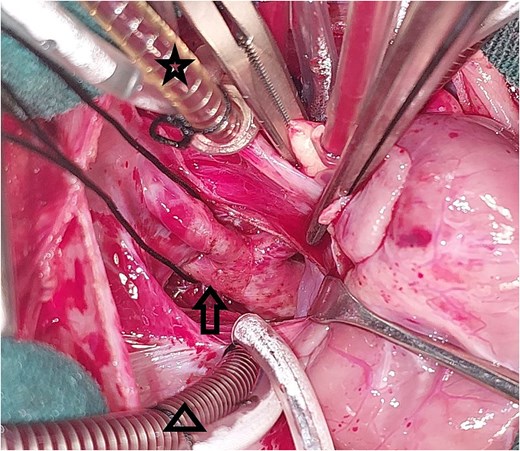

A 20-day-old boy with an unremarkable perinatal history was referred to the pediatric emergency department with respiratory distress. The physical examination revealed poor general condition and central cyanosis. The pulses were bounding in both brachial arteries but the femoral arteries were not palpable. A systolic murmur grade 4/6 was heard along the left sternal edge. The liver was enlarged 2 cm below the costal margin. Transthoracic echocardiography (TTE) was performed and revealed infracardiac TAPVC with associated CoA. Computed tomography angiography (CTA) confirmed the diagnosis of CoA (Fig. 1), and for technical issues, the pathway of CPC was not apparent on CTA. TTE was repeated and the drainage of the CPC into the portal vein was confirmed. The heart team at our hospital decided for urgent surgical repair. At first, the repair of CoA was performed through left thoracotomy with patch plasty technique since the stenosis was too long, and it was not possible to perform resection and end-to-end anastomosis. Then, through median sternotomy, the pericardium was opened, and a total cardiopulmonary bypass (CPB) was prepared. The heart was arrested with an antegrade cold blood cardioplegic solution. The CPC was seen behind the pericardium (Fig. 2). The VV was descending crossing the diaphragm, and it was dissected and controlled (Fig. 3). The heart was lifted out of the pericardium and a long incision was made in LA, and a parallel incision was made in the CPC (Fig. 4). A wide anastomosis was performed between these two incisions thus connecting the CPC into LA. The VV was permanently closed. RA was opened, and a small ASD was closed. The remainder of the operation was completed uneventfully. The patient was weaned off the CPB with stable hemodynamic conditions on low-dose inotropes (milrinone, epinephrin). Postoperative TTE showed normal pulmonary venous drainage without any gradient across the anastomosis, and excellent repair of CoA. After 48 hours on mechanical ventilation, the patient was extubated, and discharged from the ICU after 5 days. On one year follow-up, the patient was with normal growth, and in very good general condition without any complaints. TTE during the follow-up period revealed normal flow in the pulmonary veins.

Intraoperative image showing the pulmonary venous confluence after lifting the heart out of the pericardium: The triangle points to the pulmonary venous confluence, and the arrow points to the vertical vein that crosses the diaphragm.